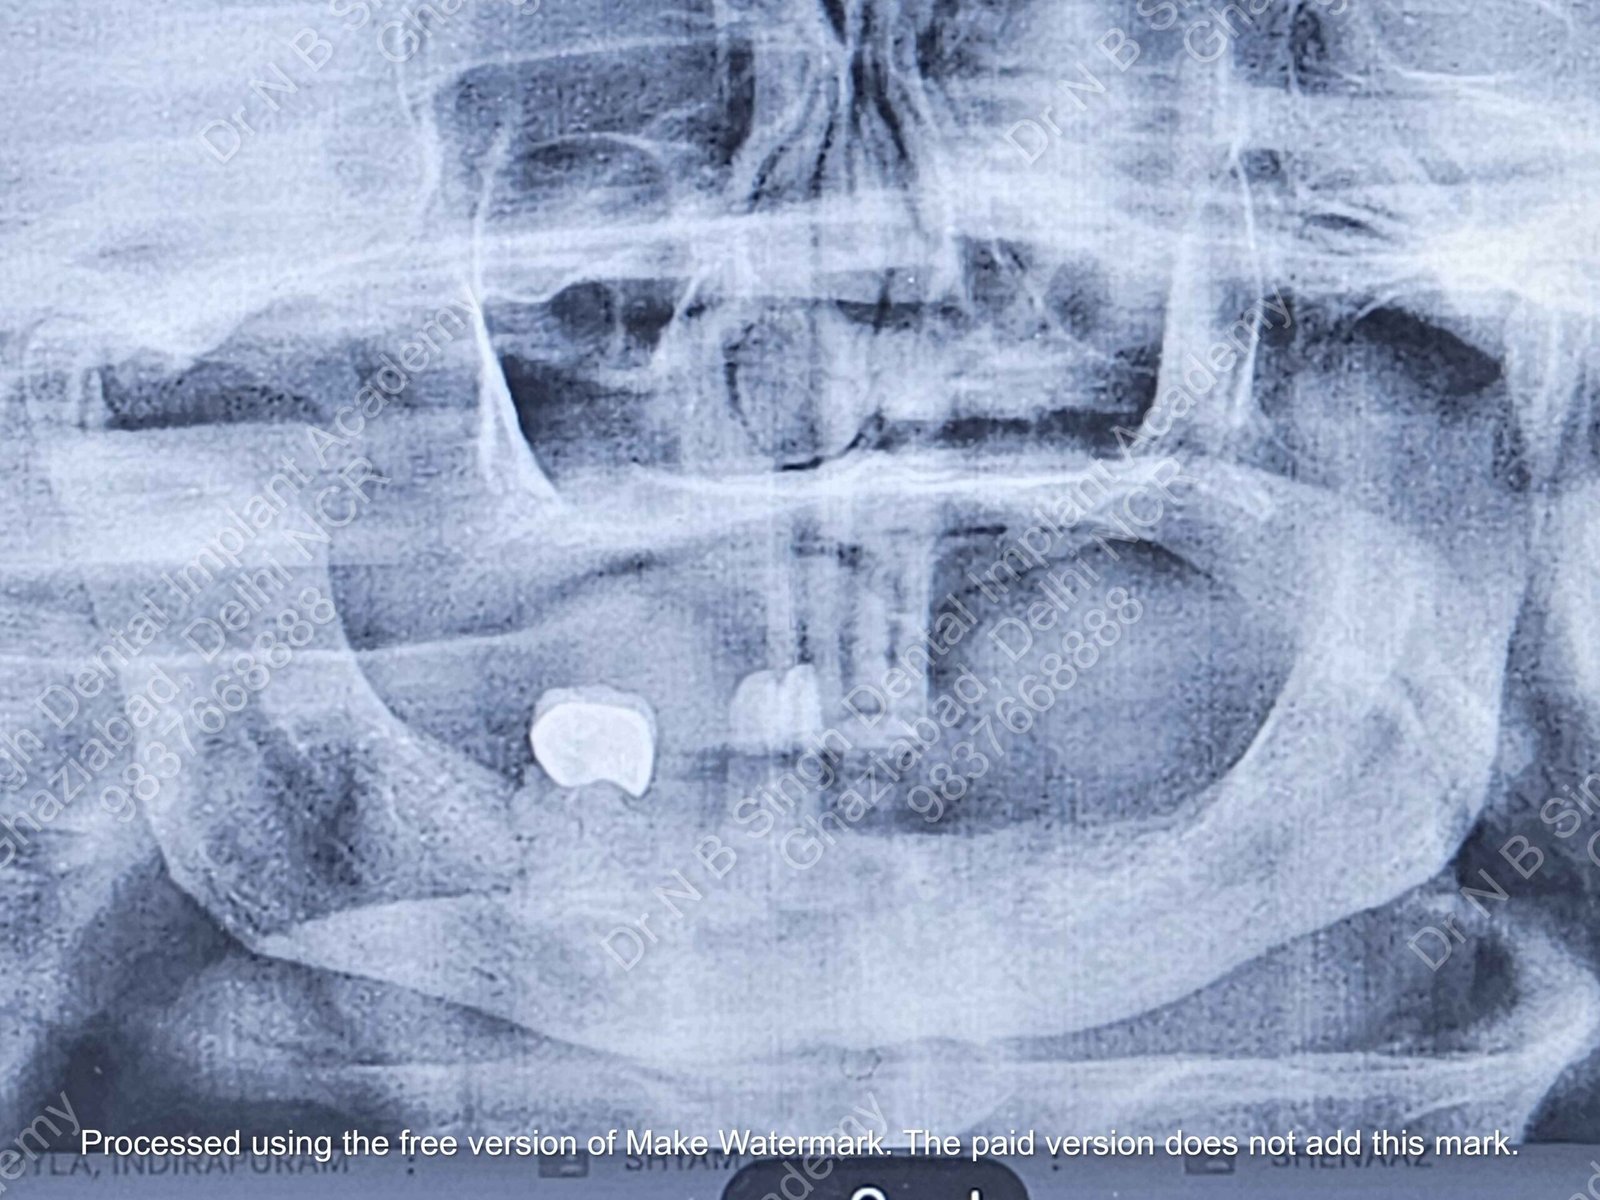

A008 Basal implants – af-qurs 1

Dr. N.B. Singh